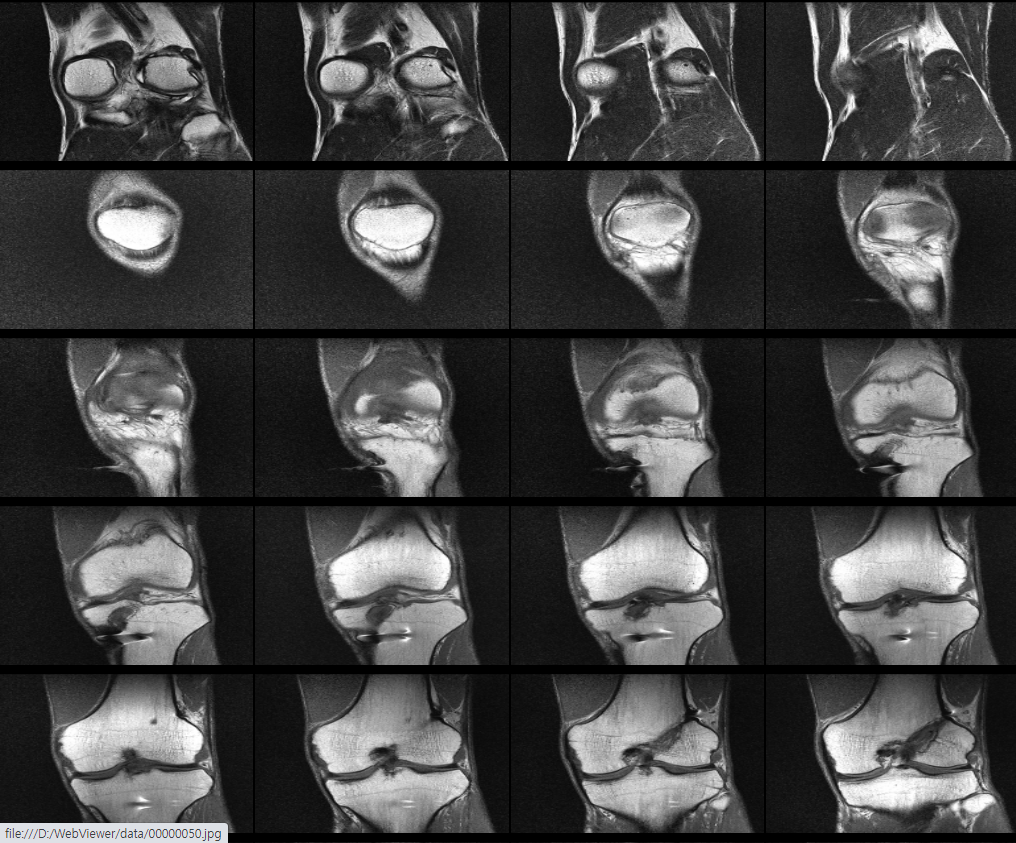

무릎 십자인대 재건술 후 약8년이 지난 지금 mri를 찍었습니다. 판독부탁드립니다ㅠㅠ

약 8년전 무릎 전방십자인대 재건술을 했는데 , 운동관련 직종이다 보니 , 운동을 많이 합니다.

최근들어 무릎에 불편한 통증이 있어 mri를 찍었는데 ,

활막염이라는 말만 들었는데 , 여러 선생님들의 의견을 듣고 싶어 사진올립니다. 판독해주시면 정말 너무너무

안녕하세요. 채홍석 의사입니다. MRI 퀄리티가 나빠서 판독은 어렵겠네요.